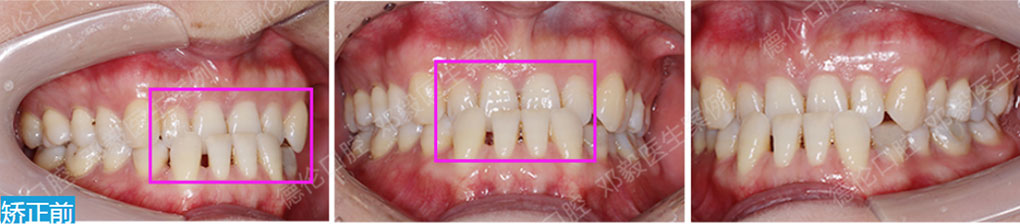

矯治采用兩種不同的厚度的膜片(牙套),發揮兩種不同膜片的各自優勢,在有效的作用時間內,矯治效率、矯治目標達成和舒適度方面較普通隱形矯正方式有明顯提升。

厚薄兩種矯治器,每周替換有利于牙齒位置的準確控制